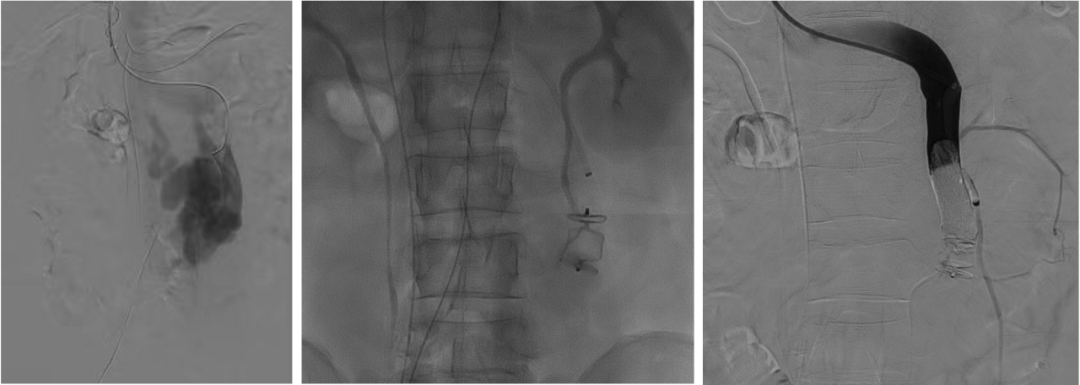

至肠系膜上动脉行间接门静脉造影,未见门静脉显影,可见巨大异常分流道,遂至脾动脉行间接门脉造影可见门静脉异常纤细,肠系膜下静脉见异常分流道形成

以微导管行肝动脉标记辅助穿刺,门静脉造影显示血流呈离肝状态

超选至肠系膜下静脉异常分流道,予以栓塞18mm的Amplatzer vascular plug及适量25%生物胶,造影示异常分流道消失

8mm覆膜支架释放于肝内穿刺道,考虑门脉纤细,遂以6mm球囊后扩张

异常分流道栓塞后,再次行门静脉造影,血流呈向肝状态,食管胃底曲张静脉较前更显著,微导管超选至曲张的胃冠状静脉,予以弹簧圈及25%生物胶栓塞,造影示曲张静脉消失,肝内门脉显影较术前显著改善